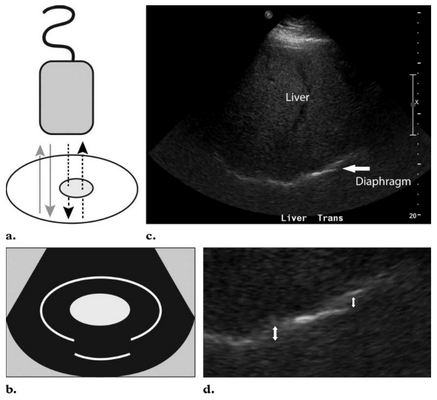

3. Реверберация - это многократное возвращение эхо-волны на трансдуктор, которое на экране выглядит как множество белых линий, параллельных исследуемой поверхности (1;5). Очень сильная реверберация называется «хвост кометы».

Этот артефакт наблюдается на границе мягких тканей или жидкостей с газом, и знание его помогает в обнаружении газовых структур. В норме реверберация имеет место при сканировании любых структур, содержащих газ - лёгкие, кишечник, желудок. Именно из-за этого артефакта ультразвуковая диагностика лёгких невозможна, а УЗИ желудка и кишечника требует особенной тщательной подготовки.

Обнаружение же газа там, где его в норме не должно быть, является ультразвуковым маркёром серьёзной патологии.

Особенное значение имеет обнаружение этого артефакта для диагностики таких острых состояний, как пневмоперитонеум и эмфизематозные изменения органов.

Эмфизематозные изменения тканей имеют место при инфицировании их анаэробной микрофлорой, продуцирующей газ. Как правило, эти состояния протекают очень остро, и их своевременная идентификация во многом определяет успех лечения.

При пневмоперитонеуме артефакт реверберации проявляется как яркие лучи, идущие из-под диафрагмы при трансабдоминальном сканировании в дорсальном лежачем положении животного. Причиной пневмоперитонеума (3;5) могут быть:

Необходимо помнить о том, что артефакт реверберации говорит только о наличии пневмоперитонеума, а не о его источнике .

Рис. 20. Артефакт реверберации.

Яркие гиперэхогенные точки - это пузырьки газа. Гипоэхогенные полосы под ними - это реверберация.

Рис. 22. Артефакт реверберации. В этом случае артефакт создаётся воздухом в поддиафрагмальном пространстве и является ультразвуковым маркёром пневмоперитонеума. На этом снимке присутствует и второй артефакт - периферическое усиление позади жидкостных структур.